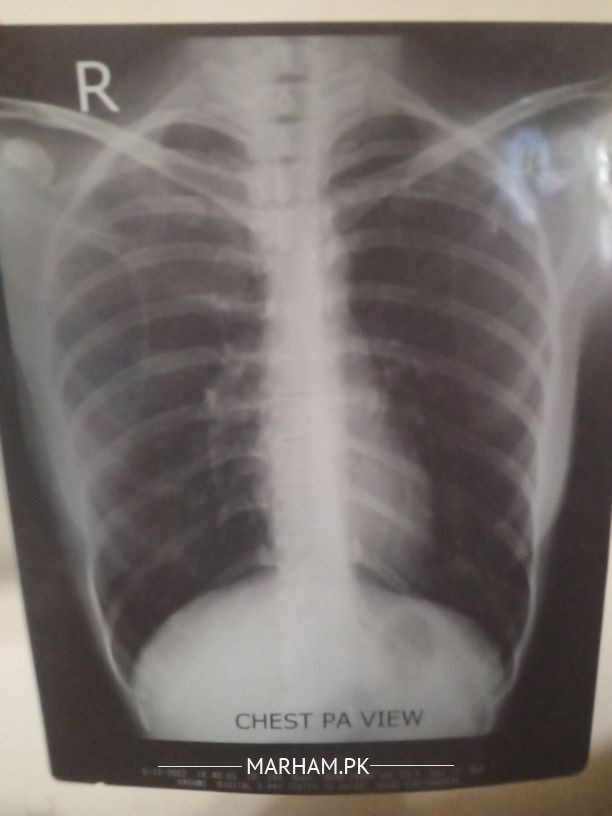

aoa mgy saans Ki problem ha Matti or dhoain m saans tang hoti ha khansi hoti ha bhok Ni lagti jisam All Time garam rheta ha weight bht Kam ha 36 kg din bdin Kam ho raha ha sath reports bhej rahi hn please check KR k help kren

Nothing significant in reports, detailed history required for better understanding, better to have an online or physical consultation.

Aapki reports sari theek Hain.Allergy Ka blood test aur X-ray men pata Nahi chalta.Proper history aur clinical examination se pata chalta hai .

Saans men dushwari ke liye steroid inhaler,anti allergic se faida hoga, nebuliser bhi araam dega.

Weight loss ki wajah ko mazeed dhoondna parega.

Acchey pulmonologist se check kerna chahiye.Antibiotics ki zaroorat Nahi hai